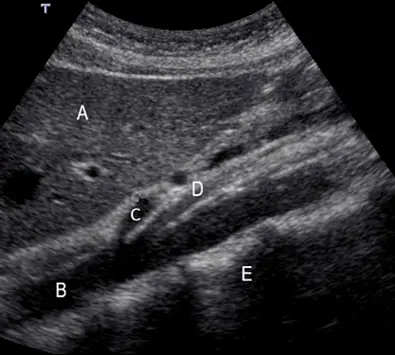

下圖為腹部中線超音波的縱向影像,編號C應為下列何者?

本圖為腹部正中線的縱向超音波影像,掃描探頭位於劍突下(subxiphoid)並作縱切。根據解剖學位置與超音波特徵,影像中各編號代表的結構如下:

- 編號 A (Liver):為肝臟左葉(left lobe of liver),位於影像的最淺層(前方),呈現均勻的中等回音實質結構。

- 編號 B (Abdominal Aorta):為腹部主動脈,呈現為一條管壁較厚、具高回音且內部無回音(anechoic)的管狀結構,位於肝臟後方。

- 編號 C (Celiac Trunk):為腹部主動脈的第一個主要前向分支,即腹腔動脈幹。在此縱切面上,它在橫膈膜下方不遠處分出,角度較為垂直。

- 編號 D (Superior Mesenteric Artery, SMA):為腹大動脈的第二個主要前向分支,即上腸系膜動脈。它緊接在腹腔動脈幹下方(約 1 公分處)分出,並以銳角與腹大動脈平行向遠端(尾側)延伸。

- 編號 E (Spine):為脊椎(椎體),位於腹大動脈的後方,表現為表面呈強回音(hyperechoic)且伴隨後方聲影(acoustic shadowing)的結構。

在腹部正中線的縱向超音波掃描中,辨認血管結構的首要關鍵是觀察其分支型態。腹部主動脈(B)位於脊椎(E)前方,由頭側向尾側掃描時,最先看到的前向分支是腹腔動脈幹(Celiac trunk, 編號 C),緊接著在其下方分出並與主動脈平行走向的則是上腸系膜動脈(SMA, 編號 D)。由於題目特別詢問「編號C」,依據超音波解剖學特徵,C 確定為腹腔動脈幹。